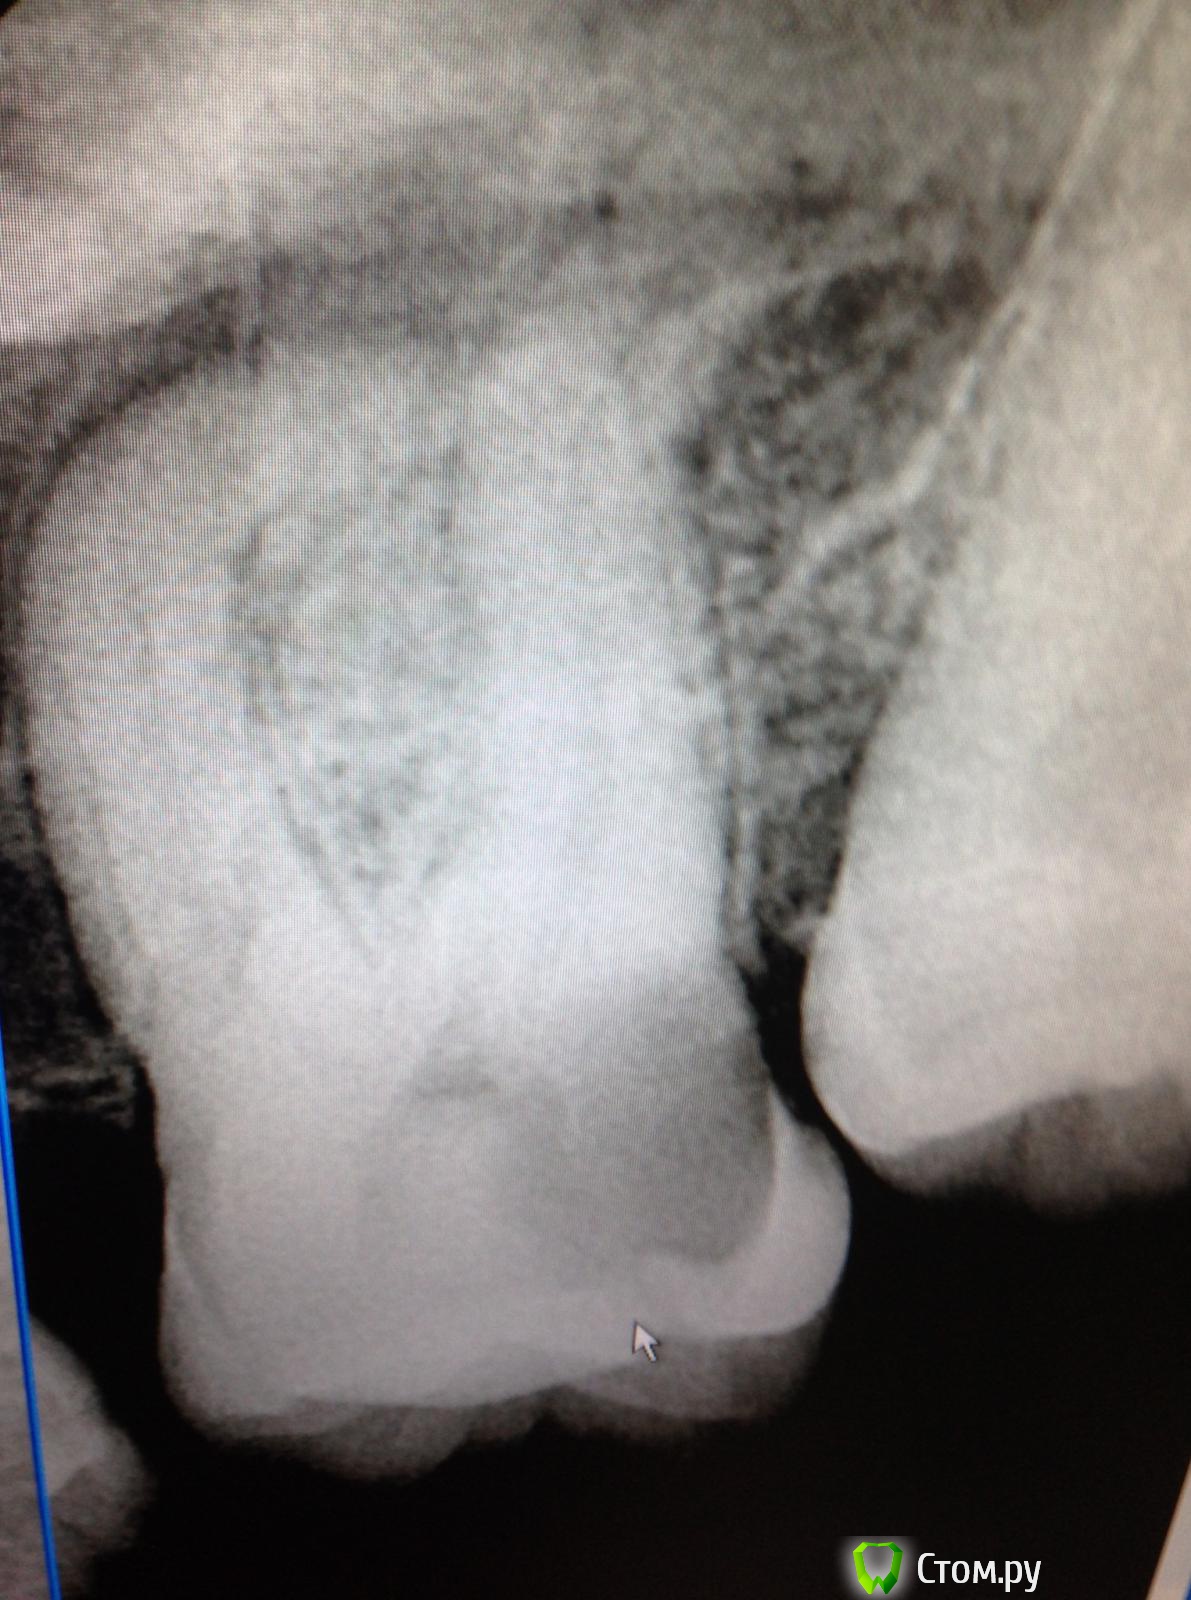

SSTi Опубликовано 2 сентября, 2014 Автор Поделиться Опубликовано 2 сентября, 2014 Кейс позора) В общем история такова. Это один из моих первых пациентов, если не первый. Только начал работать. Наконечник толком не умел держать. Ну в общем зеленый-зеленый. Диагноз не помню(пульпит или периодонтит). Это сделал я, признаюсь(года 2 назад) )))без коффера, метазоном, огромная залипуха и супер штифт на 2 мм в канале. 1 пустой. Естественно это дало обострение. Боль при накусывании и все дела. Переделал с удовольствием. Планируется вкв и мк. 3 Ссылка на комментарий

SSTi Опубликовано 19 сентября, 2014 Автор Поделиться Опубликовано 19 сентября, 2014 Новая кривулина. Начало. Попросил доктор знакомый полечить...)Неделю боли на накусывание. Иррадиируют в левый висок. Зуб 27. Внешне все ок. Маааленькая точечка в фиссуре. Шестерки нет. Делаю снимокТааааак. Позвонил доктору, сказал , как я счастлив, и приступил. Преп. Коффер. Дистально на уровне десны. Небный дистальный бугор ушел. В полости небольшой склероз. Мб сразу прошелся. Вообще без проблем. Только при хрусте файлов я чуть вспотел в области крестца))) расширились до 30.04 и дальше ручками 35.02. Мб 2 пока не нашел. Сулькус раскрыл - но там глухо. Поищем в следующий раз. Дистальный сначала только до уровня , как на снимке, потом прошел. Тоже 30.04 и 35.02. Небный- последние 3-4 мм дались с трудом. Но прошли. До 35.04 и 40.02. Мылись, сушились, кальцифицировались. Времянка. Продолжение следует 3 Ссылка на комментарий